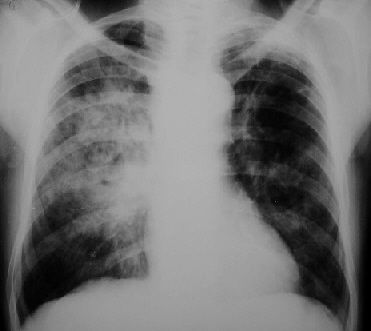

MANIFESTACIONES CLINICASNeumonia Tuberculosa: Primoinfección gralmente asintomatica o paucisintomatica Afecta fundamentalmente a lobulos medios o inferiores Se acompaña de adenopatias hiliares Forma de predominio en la infancia PLEURITIS TUBERCULOSA puede ser la manifestacion de una primoinfección Reactivación Tuberculosa Fundamentalmente segmentos apicales y posteriores de los lobulos superiores CAVITACIÓN Clinica insidiosa: Febricula, malestar general, pérdida de peso, sudoración nocturna, tos persistente y expectoración en ocasiones hemoptoica Dx baciloscopia

TUBERCULOSIS MILIAR O DISEMINADA Se produce por diseminación hematogena en personas con alteración grave del sistema inmune Mas fcte en ancianos Patognomonico tuberculos en la coroides, pero poco fcte Rx de torax Patrón micronodular tipico en grano de mijo